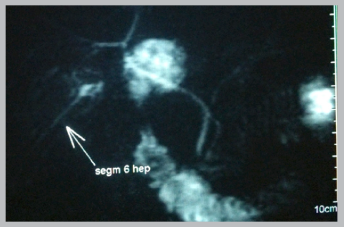

Se programó una colecistectomía laparoscópica, durante la cual se encontró como hallazgos una vesícula de paredes gruesas, distendida, de 7x4x3 cm de diámetro, emplastronada con epiplón; conducto cístico fino y corto; y se evidenció la presencia de un conducto del segmento VI anómalo con terminación a nivel del conducto cístico; foto 2. No se presentaron complicaciones durante la cirugía y la evolución post- quirúrgica fue favorable. Se realizó una colangioresonancia de control dos semanas después de la cirugía, la cual demostró un conducto hepático funcional que drenaba el segmento hepático VI; foto 3.

Foto 3 Colangioresonancia de control. se observa un conducto hepático funcional que drena el segmento hepático VI.